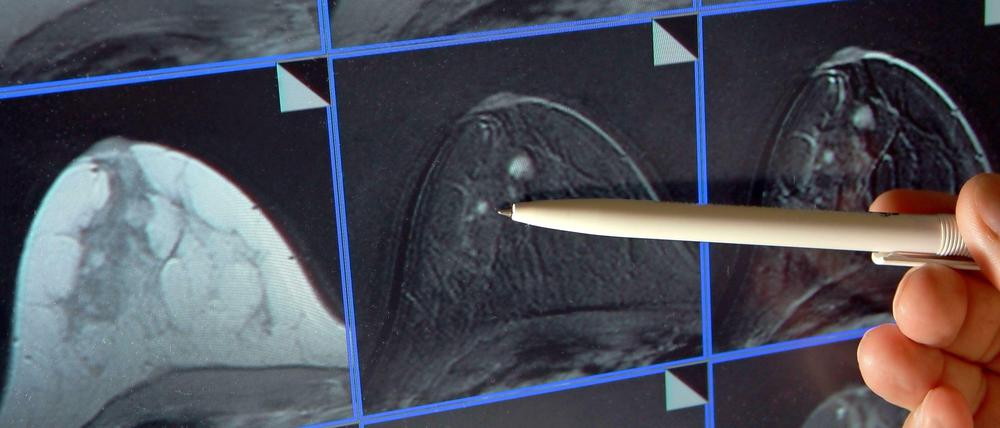

Berlin und Brandenburg: Gemeinsames Krebsregister für die Region

Im Kampf gegen Krebs hoffen Ärzte, Kassen und Politik auf Fortschritte durch bessere Daten. Deswegen sollen Berlin und Brandenburg ein gemeinsamen Krebsregister bekommen.